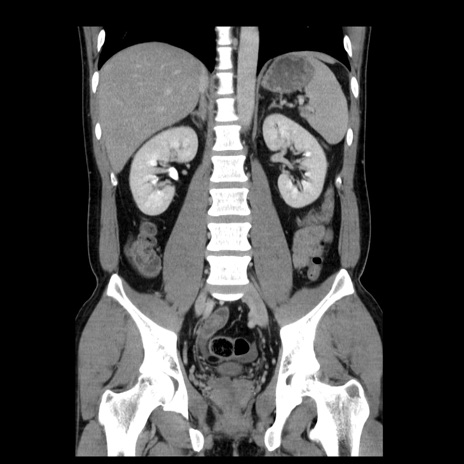

症例4(冠状断像)

【症例】30歳代男性

【主訴】腹痛、嘔吐

【現病歴】昨晩から突然の腹痛あり、その後嘔吐、軟便も出現。腹痛が改善しないため救急搬送となる。2日前にしめ鯖の食事歴あり。

【身体所見】意識清明、苦悶様、BP 135/90mmHg、BT 35.7℃、腹部:平坦、やや硬、心窩部〜臍部に自発痛、圧痛あり、筋性防御+、反跳痛-

【データ】WBC 8100、CRP 0.57